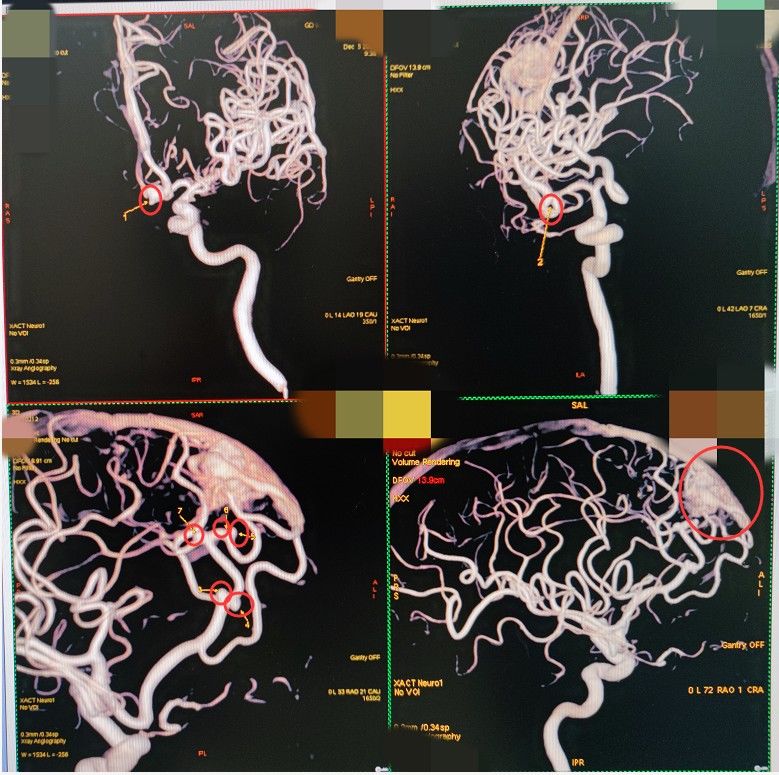

该院接诊的副院长鲁明仔细询问患者的病史,怀疑是动脉瘤或者动静脉畸形破裂导致的蛛网膜下腔出血。“脑血管造影成像下,可以清晰看到,患者右侧大脑前动脉A2段、A3段及中动脉M1段分叉处和前交通等分布着7个大小不一的动脉瘤,最大一个直径有7mm。右侧额叶有一团15mmX18mm大小的动静脉血管畸形团,犹如纠缠在一起的一团蚯蚓。”鲁明说,多发性动脉瘤本来就比较少见,但一次性长7个动脉瘤还是第一次见。

红圈处为动脉瘤和畸形团,一次性长7个动脉瘤相当罕见。医院供图

紧急完善相关术前检查后,鲁明副院长及神经外五科团队为患者实施了颅内多发动脉瘤夹闭术,一次性夹闭了7个动脉瘤,连同动静脉畸形团也一起切除。“手术足足做了12个小时,7个动脉瘤就是7个‘不定时炸弹’,一次性处理能有效地杜绝后患。”鲁明说。术后给予抗感染消炎等对症治疗后,黄阿姨将于近日康复出院。